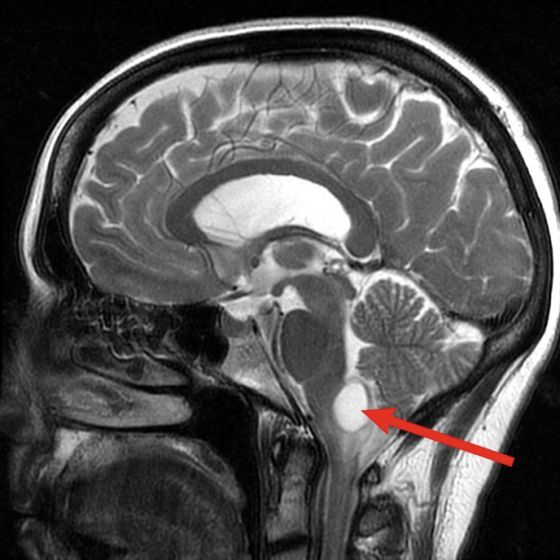

Os tumores hipervascularizados, estão localizados geralmente na base do crânio e na cabeça e pescoço, dentre eles a maioria são paragangliomas, retinoblastomas, nasoangiofibromas, meningiomas, hemangioblastomas, estesioneuroblastomas, entre outros, também pode ser ponderada a possibilidade na realização da embolização pré-operatória. Iremos descrever os principais e mais frequentes tumores hipervasculares que a NRI pode estar auxiliando no tratamento cirúrgico.

A base do crânio é a área que separa o cérebro de todas as outras estruturas ao seu redor. E está localizado atrás dos olhos e do nariz. Quando tumores ou outras anormalidades se formam nesta área, eles podem afetar os nervos muito sensíveis ao seu redor. Os tumores podem ser difíceis de alcançar e a cirurgia representa um risco devido à proximidade do cérebro e à proximidade de vasos sanguíneos e nervos importantes. A cirurgia da base do crânio é complexa e requer uma abordagem de equipe multidisciplinar experiente, dentre elas a neurradiologia intervencionista.